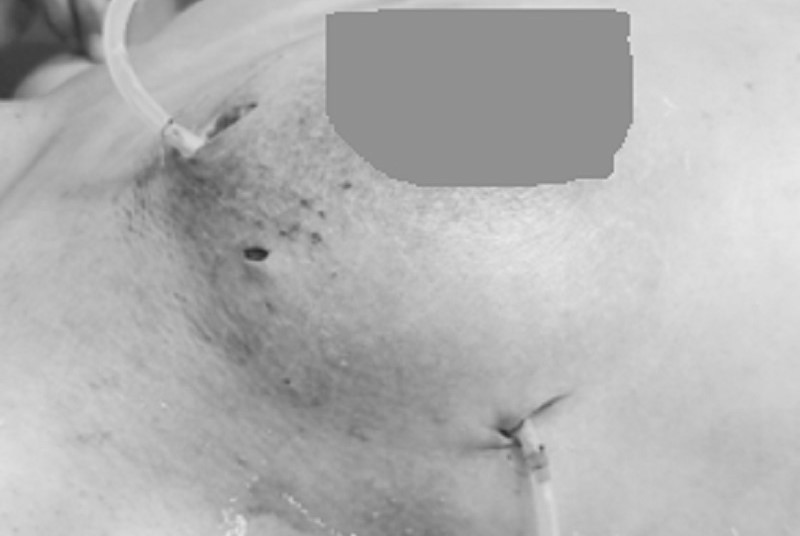

Để xử lý ổ nhiễm trùng, kíp phẫu thuật đã tiến hành can thiệp ngoại khoa nhằm loại bỏ các tổ chức mô tuyến vú và mô mỡ đã bị hoại tử. Trong quá trình phẫu thuật, các bác sĩ đã tháo lưu khoảng 150ml hỗn dịch mủ và dịch tiết viêm, đồng thời đặt dẫn lưu để bơm rửa khoang áp xe liên tục. Hiện tại, tình trạng bệnh nhân đã ổn định và đang tiếp tục được theo dõi điều trị nội khoa hậu phẫu.